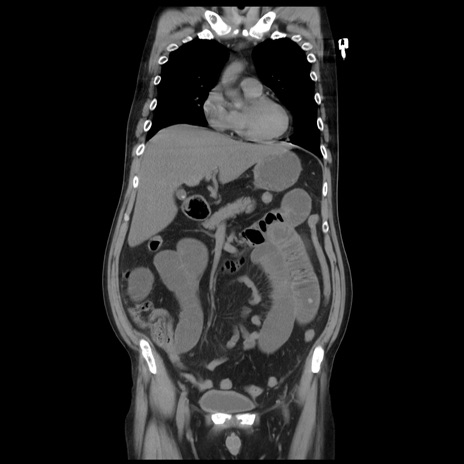

矢状断像

【症例】 60歳代男性

【主訴】 腹部膨満、嘔吐

【現病歴】5日前頃より倦怠感を認め食事量減少し4日前の朝嘔吐、食事摂取困難となった。 3日前近医受診し点滴施行され整腸剤などを処方された。 当日他院を受診し、腹部膨満著明、炎症反応の上昇(CRP10.8、WBC11200)あり、紹介受診となる。

【身体所見】 意識JCS1 受け答えがはっきりしないBP 111/57mHg、 P 67bpm、、BT35.2°C、SpO2 97%(RA)、 腹部:膨隆、打診で鼓音あり、全体的に圧痛有り、腸蠕動音(-)、反跳痛ははっきりせず。

【データ】WBC 11400、CRP 14.20